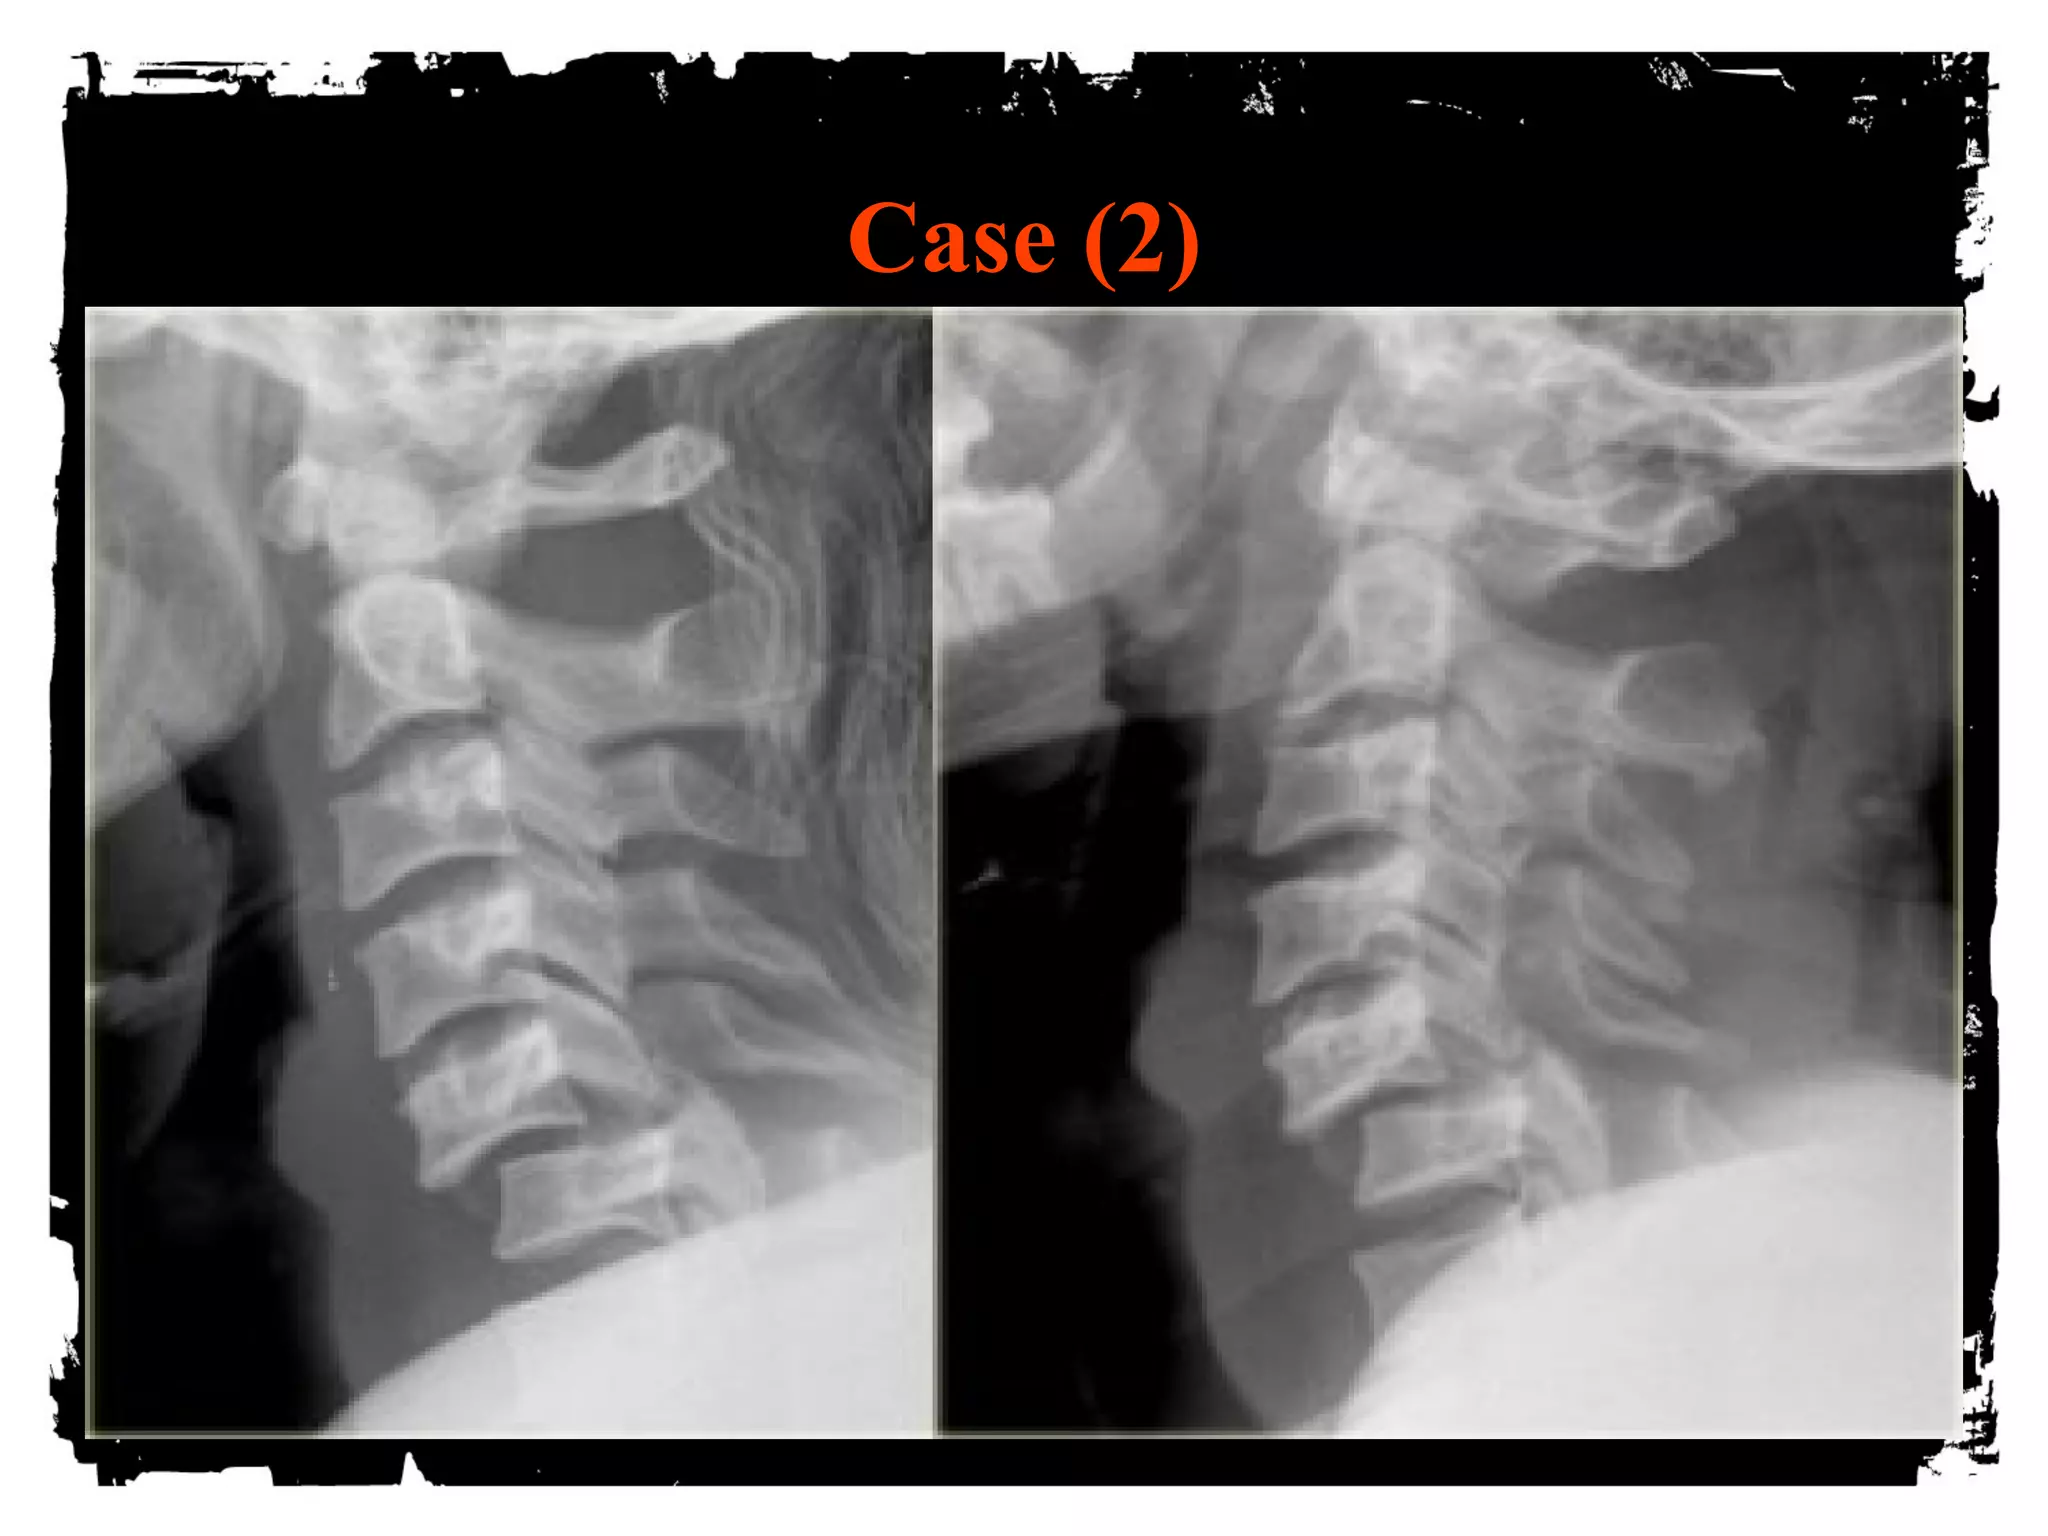

Case (2)

Bilateral Facet Dislocation

Extreme hyperflexion

Anterior dislocation of articular masses (disruption of

posterior ligament complex,PLL,disk and ALL).

Complete dislocation: dislocated vertebra anteriorly

displaced ½ of AP diameter of vertebral body

Unstable ( high incidence of cord damage)